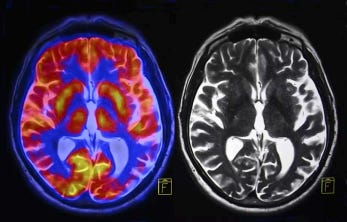

At the same time, being overly stressed is potentially dangerous. Chronic stress can cause inflammation in the brain, due to prolonged exposure to hormones. This inflammation can potentially alter memory or mood. Stress also increases the risk of developing other neurological conditions like dementia, depression, migraines, and even a stroke.

Acute stress has the ability to temporarily boost the brain’s function, though chronic stress may lead to shrinking the hippocampus. This is because the human brain’s neuroplasticity is flexible. Changes to our environments may lead to minor changes in our brain’s structure. Overall, steps should be taken to reduce the toll that stress takes on the body by developing healthy coping mechanisms such as meditation, exercising, breathing methods, etc.